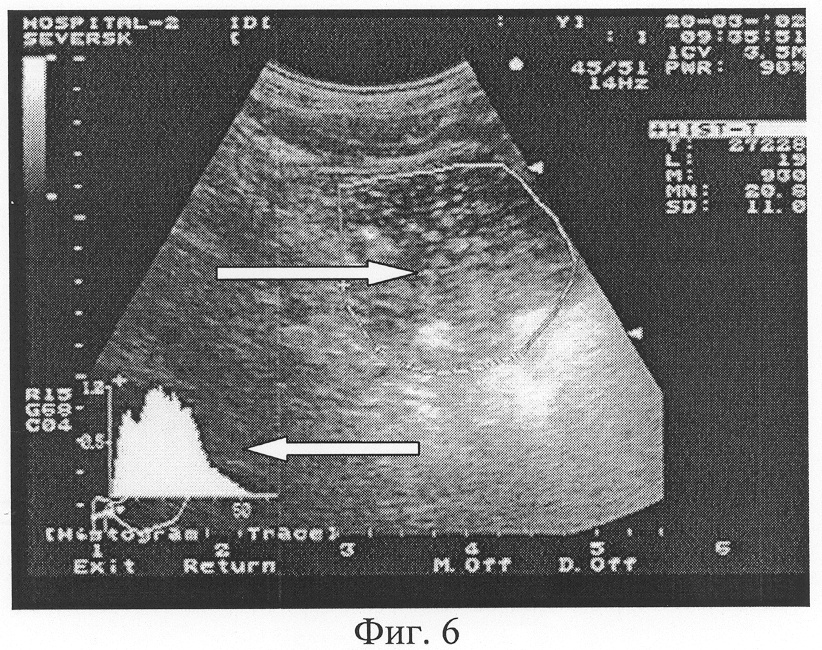

Способ-прототип несет в известной степени элемент субъективизма при оценке характера содержимого двенадцатиперстной кишки, требует определенной наработки, опыта в проведении заключения по характеру содержимого ДПК. Это и вызвало необходимость разработки и внедрения нами предлагаемого способа ультразвуковой оценки содержимого кишки с использованием гистографии. Характеристика полученной гистограммы проводится по двум показателям: «преобладающей» эхоинтенсивности MN и оценке графической кривой гистограммы. Построенная гистограмма исследуемого очерченного участка содержимого ДПК оценивает в конкретных цифрах показатель «преобладающей» эхоинтенсивности MN исследуемой зоны (Фиг.3-6). Чем выше значение MN, тем больше плотность среды. По виду распределения на гистограмме и по показателю, соответствующему количеству пикселей с «преобладающей» эхоинтенсивностью, проводят оценку эхогенности и степени неоднородности содержимого двенадцатиперстной кишки в конкретных единицах величины MN. Распределение эхоинтенсивности при графической гистографии проводится в виде построения аппаратом ультразвуковой диагностики своеобразной графической кривой (Фиг.3-6). Если гистограмма имеет вид явно выраженного высокого острого пика в графическом ее изображении, то очерченный участок изображения соответствует однородной среде, что является нормальным показателем при оценке содержимого ДПК после приема жидкости натощак. Кроме этого, чем выше число пикселей с данной эхоинтенсивностью, тем графический пик более острый и высокий с относительно узким «столиком» основания графической кривой – значит среда более однородна (Фиг.3-5). Графическое распределение в виде «столика» с относительно широким основанием и несколькими пиками означает неоднородность среды, что свидетельствует о нарушении моторно-эвакуаторной способности верхних отделов желудочно-кишечного тракта (Фиг.6).

В результате проведенного исследования 237 пациентов нами определен норматив значения показателя «преобладающей» эхоинтенсивности MN содержимого двенадцатиперстной кишки в выделенном участке изображения, равный 8-12 единицам. В случае снижения этого показателя считаем правомочным определить содержимое желудка как – «эхогенность содержимого двенадцатиперстной кишки снижена» (Фиг.5). Эти ультразвуковые параметры будут характерны для задержки эвакуации содержимого из двенадцатиперстной кишки. В случае превышения данных значений MN показатели эхогенности содержимого ДПК будут главным образом указывать на снижение измельчающей функции желудка, ускорение эвакуации содержимого из желудка в двенадцатиперстную кишку (Фиг.3, 6).

Однопиковая кривая гистограммы с узким основанием предполагает однородное содержимое исследуемого объекта (Фиг.3-5), при регистрации нескольких пиков и широком основании графической кривой дается характеристика содержимого как неоднородное (Фиг.6), причем количество пиков и ширина основания будут характеризовать степень их выраженности.

Фиг.6. Трансабдоминальное ультразвуковое исследование двенадцатиперстной кишки. Гистографический анализ содержимого ДПК с использованием зоны маркера в виде очерченной ее площади (обозначена стрелкой ). Значение показателя преобладающей эхоинтенсивности MN содержимого двенадцатиперстной кишки составило 20,8 единицы (норматив 8-12 единиц). Графическая кривая гистограммы (обозначена стрелкой ) с тупыми множественными пиками подтверждает факт неоднородного содержимого кишки.